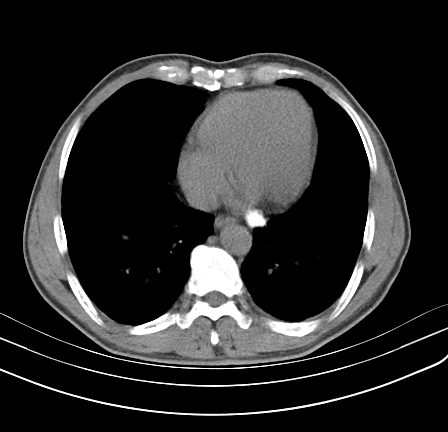

以下是引用影像孺子牛在2009-5-20 23:18:00的发言:[br]左侧后心膈角处类椭圆形钙化灶,最常见的是淋巴结钙化,但太大了不支持,其它如食管囊肿钙化、实性畸胆瘤等。何东西钙化真不好定。

以下是引用zbp537在2009-5-20 20:52:00的发言:[br]钙化灶,来源不好说。